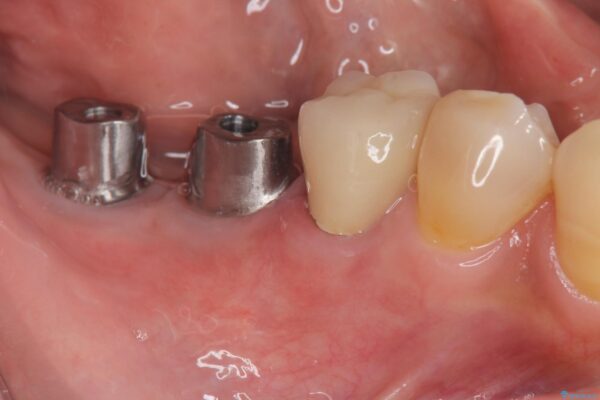

治療中

奥歯から膿のにおいがする インプラントによる機能回復 治療中画像 奥歯から膿のにおいがする インプラントによる機能回復 治療中画像 奥歯から膿のにおいがする インプラントによる機能回復 治療中画像 奥歯から膿のにおいがする インプラントによる機能回復 治療中画像